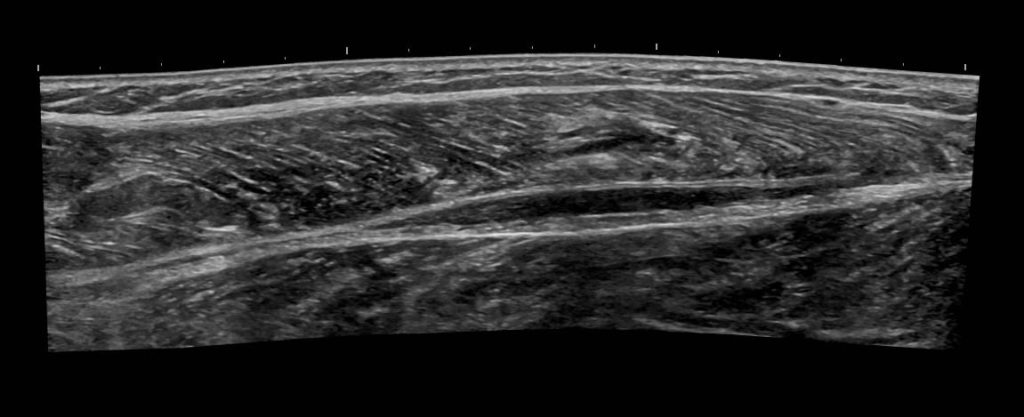

Visualizza 4: Vista longitudinale panoramica del polpaccio

Immagine 4: Vista longitudinale panoramica del polpaccio che mostra la raccolta di liquido attorno al tendine del plantare rotto.